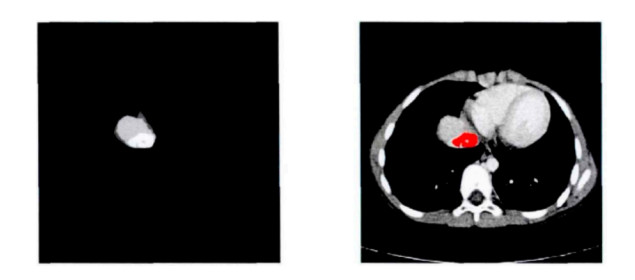

Figure 5.  Original CT image and smooth, segmented liver image

Figure 6.  Multi-threshold OTSU segmentation of the sixth layer of liver CT images